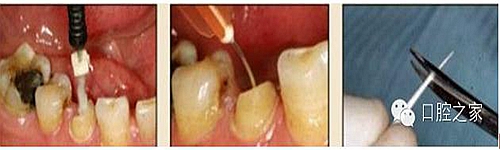

2. 清除根管壁殘留物

圖3:根管內(nèi)殘留物

圖4:超聲去除根管殘留物?! ?/p>

根管壁殘留物的存在直接影響著纖維樁的粘接和固位,是纖維樁脫落的主要原因之一。由于圓形的根管鉆和根管形態(tài)不完全一致,終鉆預(yù)備完成后大多情況下樁道側(cè)壁會(huì)有不同程度的牙膠和封閉劑等殘留物附著(圖 3)。因此,建議X線檢查根管預(yù)備情況,選用超聲潔牙機(jī)更換較細(xì)工作尖進(jìn)入根管,徹底去除樁道根管壁上附著的殘留物(圖4)。使用根管銼去除殘留物時(shí),很難清除干凈;禁止使用牙膠溶劑如丁克除、氯仿等有機(jī)溶劑去除殘留物,以免破壞根尖區(qū)牙膠的封閉,或有機(jī)溶劑粘附于根管壁形成蠟?zāi)ざ绊懻辰印?#pages##